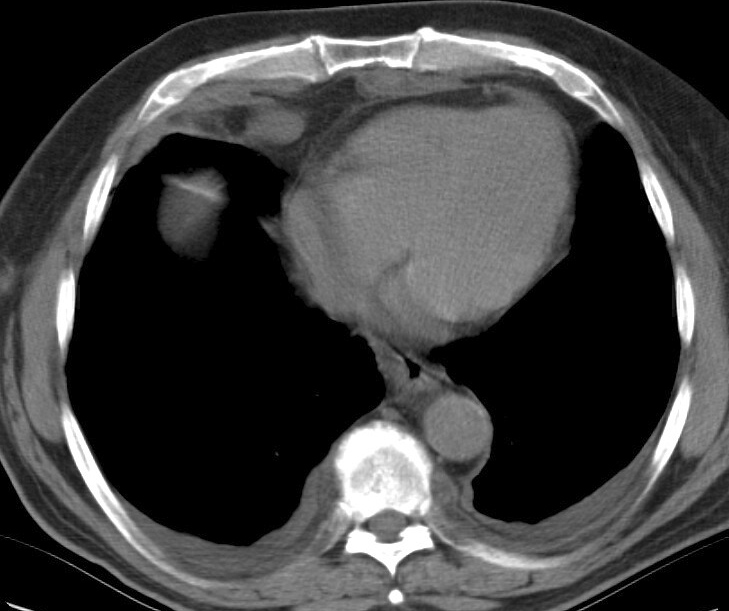

Gallery Mediastinum Lymphoma 4b

4b